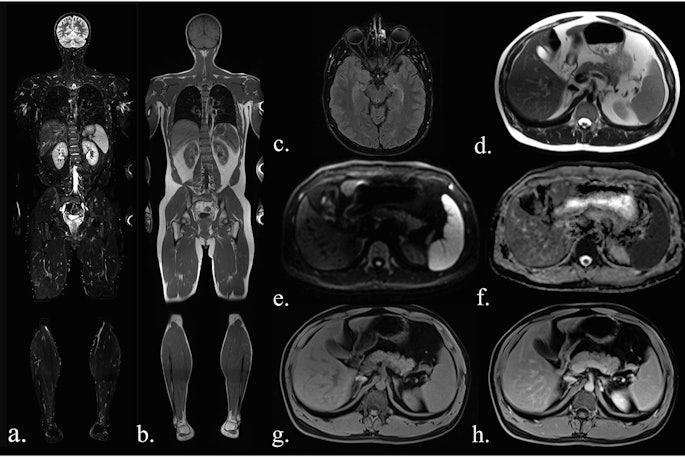

PET/MRI begins to deliver in breast cancer